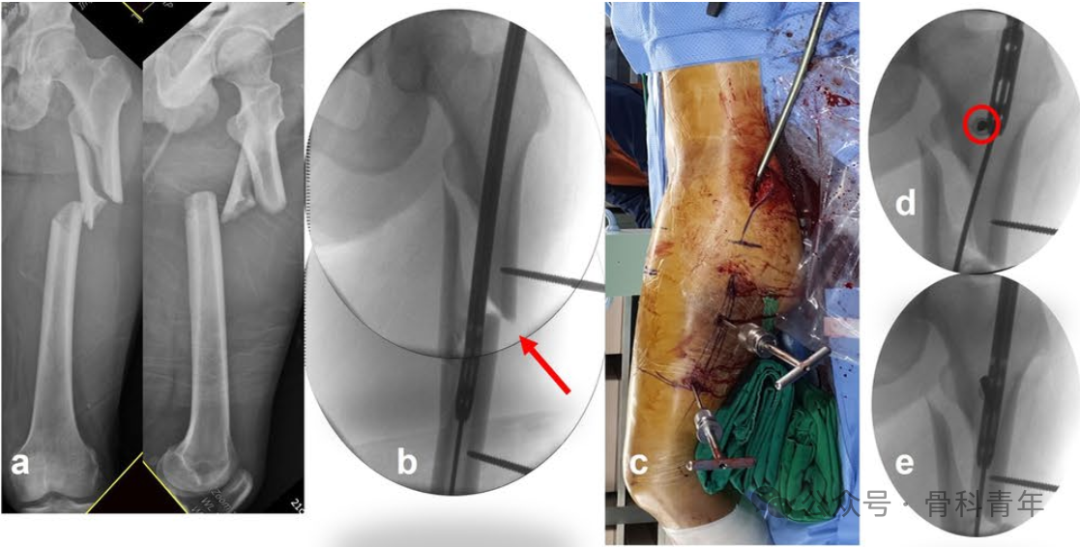

文章纳入25例在粗隆下骨折髓内钉固定中,采用阻挡钉病例,结合病例的术中透视情况,并认为在C臂机上透视移位超过1个皮质,认为复位不良,需要继续复位。

指征3:在侧位上,存在向前成角。除在冠状面的成角外,矢状面上的移位可以在侧位上体现。近端骨块在髂腰肌和外展肌群的牵拉下,容易向前成角。此时,需要将阻挡钉置于髓内钉前进方向的后方,纠正向前成角。

图片